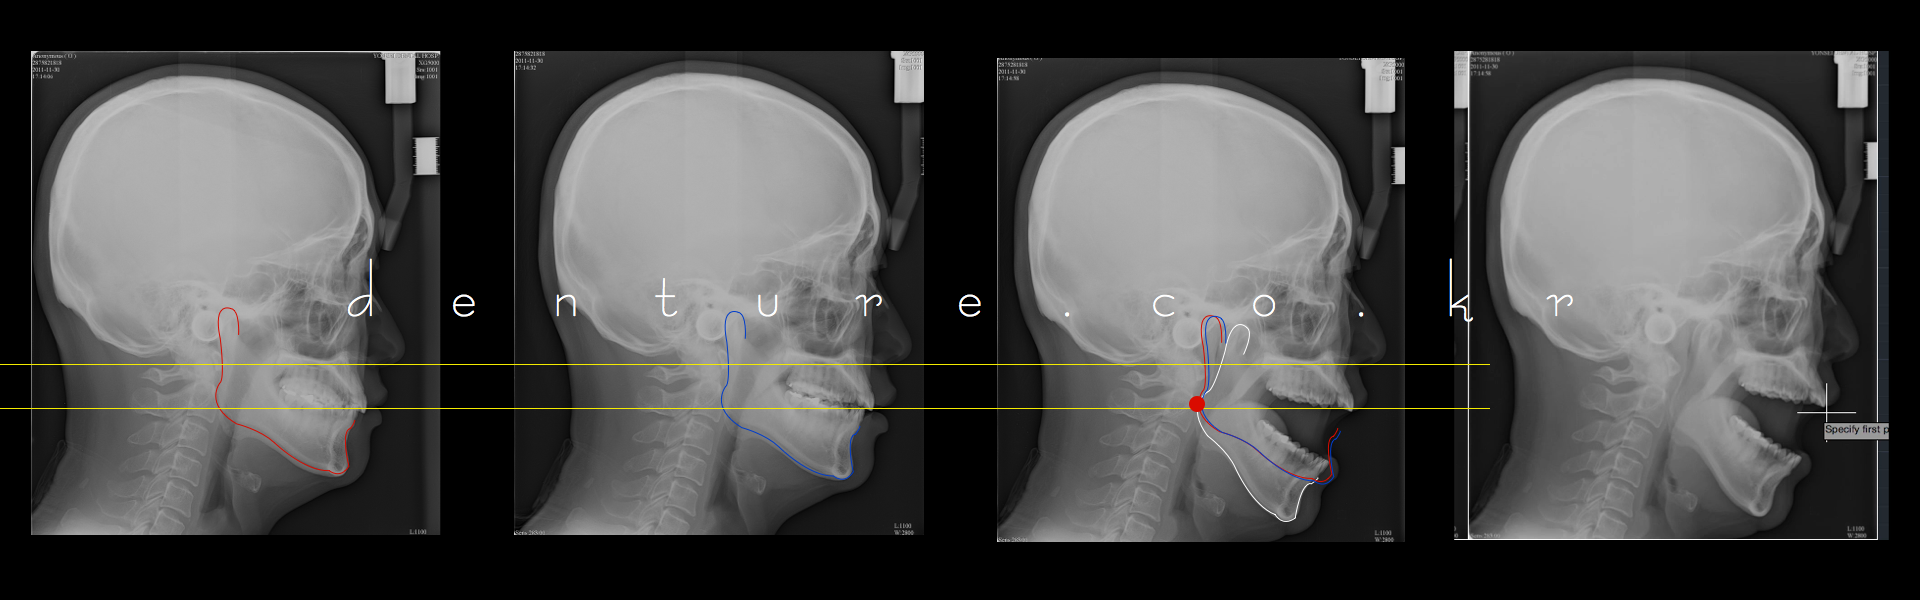

사람의 balkwill angle은 20~30 정도라고 합니다.

이런 생각도 해봅니다. 과두의 위치를 손가락으로 집어보면 대강의 위치가 나옵니다. bonwill 정삼각설과, balkwill angle을 사용하여 자신의 과두간 거리를 계산해 봅시다.

얼굴 측면에서 손가락을 귀(tragus)에서전방으로 위치하고 입을 열었다 닫았다 해봅니다. 과두가 움직입니다. 그걸 표시하고 30cm

자를 이용해 하악 절치점 까지의 거리를 눈으로 대충 식별합니다.

auto cad로 보니 저는 balkwill23도 입이작아 최대로 눈이 튀어나오게 벌려봤자 21도 입니다. 손가락 세개 들어가네요..